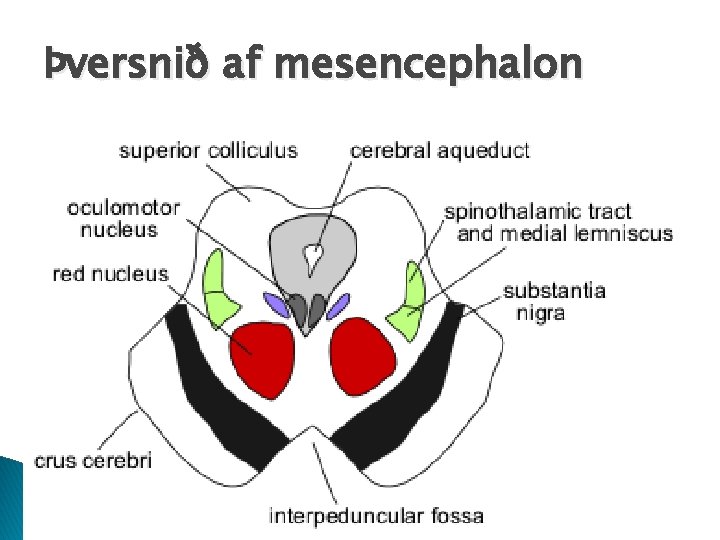

Fimm helstu svæði heilans � Mesencephalon ◦ Tegmentum �Rennur saman við brú �Inniheldur nokkra hreyfikjarna sem tengjast virkni basal ganglia �Rauði kjarninn (red nucleus) �Svarta efnið (substantia nigra) �Periaquaductal grey area �Ventral temental area ◦ Tectum (þak) �Colliculi �Superior: Tengist sjónúrvinnslu og sjónrænum viðbrögðum �Inferior: Tengist úrvinnslu heyrnaráreita �RAS – þræðir frá reticular formation

Þversnið af mesencephalon